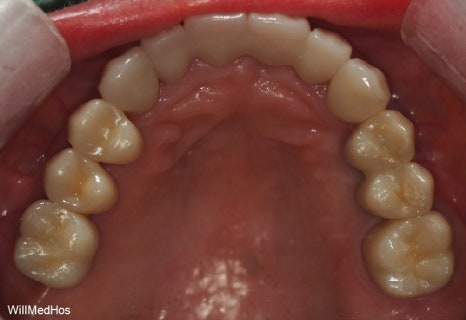

최종 치료 완료된 구강 모습입니다. 앞전의 구강 사진과 비교해보시면 자연스러운 치아의 모습이 완성된것을 확인 할수 있습니다.